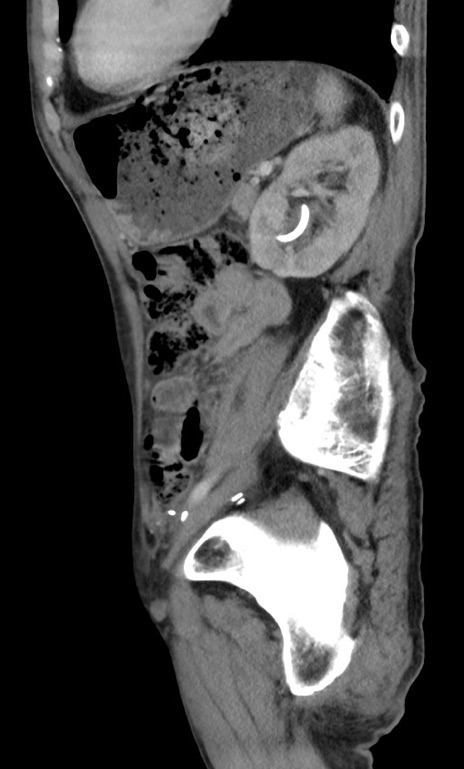

症例3(矢状断像)

【症例】 70歳代男性

【主訴】右鼠径部腫瘤、疼痛

【現病歴】本日朝より上記主訴あり、受診。

【既往歴】膀胱癌にて膀胱全摘、両側尿管皮膚瘻

【データ】WBC 5600、CRP 0.56